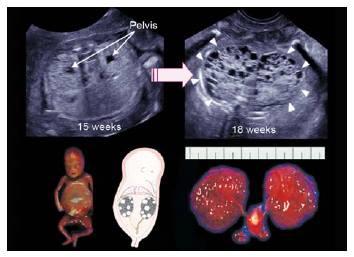

When should the kidneys and the bladder be seen?

15 weeks

bubble sign

bubble sign

Bilateral multicystic dysplastic kidney disease

unilateral multicystic dysplastic kidney disease

unilateral multicystic dysplastic kidney disease

What is the sonographic appearance of bilateral MDK?

multiple, round

various sizes

bladder not seen

olighydramnios

Poor Prognosis

What is the sonographic appearance of unilateral MDK?

multiple, round

various sizes

bladder seen

hydronephrosis